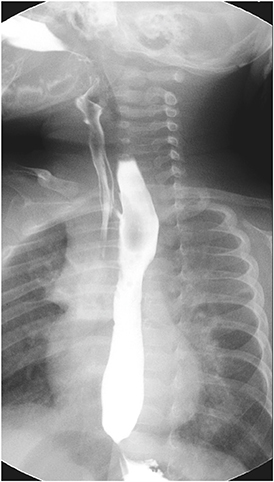

Routine esophagogram taken on postoperative day 10 still showed an evidence of fistula (

Fig. 3). Recurrence or presence of another H-type fistula had been suspected. To confirm the diagnosis, rigid bronchoscopy was scheduled under general anesthesia on postoperative day 15. However, the bronchoscopy failed to demonstrate the opening of the fistulous tract even under positive ventilation.

Fig. 3 Another H-type fistula at T2 level.